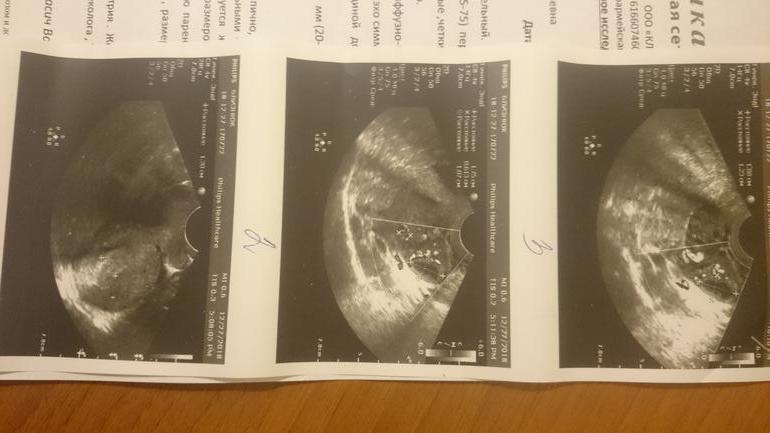

Чтобы подтвердить или опровергнуть О, сходила на УЗИ (не к своему любимому доктору - записи до нового года уже нет). Девочка попалась совсем молоденькая, во всем сомневающаяся. Как итог, увидела ЖТ, но говорит, что скорее всего осталось с прошлого цикла, в стадии регрессии. Я уточнила, что тест на О был положительным 2 дня назад. На что мне ответили: "ну тогда возможно это ЖТ этого цикла". 🤦♀️В левом Я вообще нет ни одного фолликула. Плюс эндометрий первой фазы. Отклонения миометрия в наличии, но они незначительны. Короче, я в некотором расстройстве.